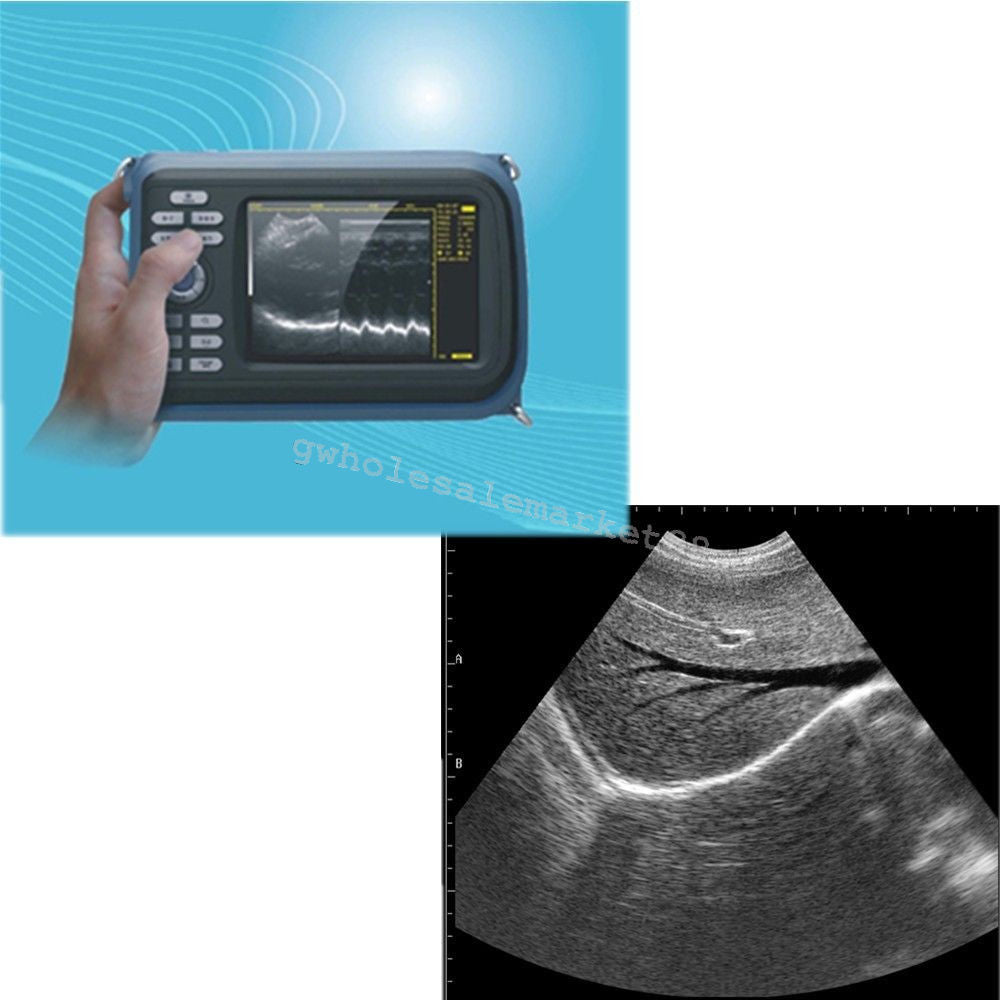

The laptop ultrasound scanner is designed for versatility and ease of use. It features both Convex and Transvaginal probes, allowing for comprehensive examinations in various settings. This scanner ensures high precision in imaging, giving healthcare providers the ability to make accurate diagnoses quickly. Because of its ergonomic design, it's easy for practitioners to operate, so they can achieve clear images with minimal effort.

One of the standout features of this laptop ultrasound scanner is its portability. Weighing less than conventional ultrasound machines, it allows healthcare professionals to bring it right to the patient’s side. Plus, the user-friendly interface simplifies the operation, making it suitable for medical staff of all experience levels. Also, the compact size ensures that it fits easily into tighter spaces, such as small clinics or in-home care environments.